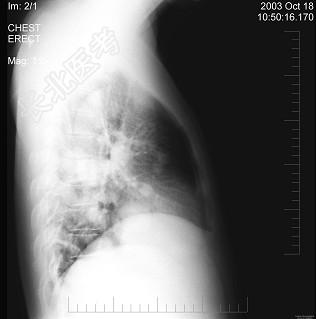

- 单项选择题男性,43岁, 胸闷、胸痛10余天,不咳嗽不发热, X线检查如图,最合理的诊断是 ( )

A、原发性肺癌

B、肺转移瘤

C、炎性假瘤

D、结核瘤

E、支气管扩张